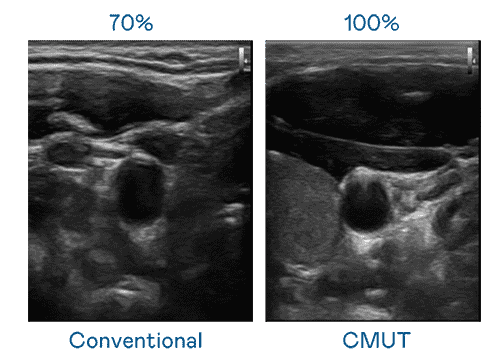

CMUT 技术是一种用电容式微机电元件来产生超音波讯号的技术。。与传统 PZT 压电式技术相比,,,CMUT 频宽增加 30%,,更宽频的超音波讯号让影像解析度大幅提升,,,,是实现高影像品质医疗超音波扫描、、促进精准医疗发展的关键技术。。。。

超音波影像的解析度高低,,,,首先取决于探头能发出的讯号频宽。。NG大舞台 CMUT 可提供高清晰的超音波讯号,,,,提供高频宽、、、高灵敏度、、影像纹理细节更高的超音波影像,,协助医护人员缩短影像判读时间及利用精准的医疗影像进行诊断。。